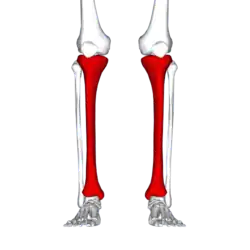

| |

| Red area represents the tibia. Pain is generally in the inner and lower 2/3rds of tibia. | |

A shin splint, also known as medial tibial stress syndrome, is pain along the inside edge of the shinbone (tibia) due to inflammation of tissue in the area.[1] Generally this is between the middle of the lower leg and the ankle.[2] The pain may be dull or sharp, and is generally brought on by high-impact exercise that overloads the tibia.[1] It generally resolves during periods of rest.[3] Complications may include stress fractures.[2]

Shin splint pain is described as a recurring dull ache, sometimes becoming an intense pain, along the inner part of the lower two-thirds of the tibia.[5] The pain increases during exercise, and some individuals experience swelling in the pain area.[6] In contrast, stress fracture pain is localized to the fracture site.[7]